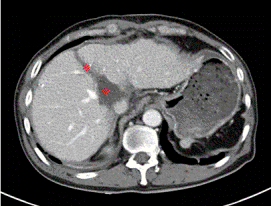

通過CT、磁共振以及三維重建的圖像來看,王先生的腫瘤位于肝臟尾狀葉,除左側(cè)可見少量肝組織以外,腫瘤已侵犯絕大部分的尾狀葉!“跟土豆差不多大!”胡偉表示,王先生的肝臟腫瘤約有5*5*4㎝大小,手術(shù)切除對(duì)于他來說是目前唯一有效的治療方案!

術(shù)前增強(qiáng)CT顯示腫瘤位于肝臟尾狀葉